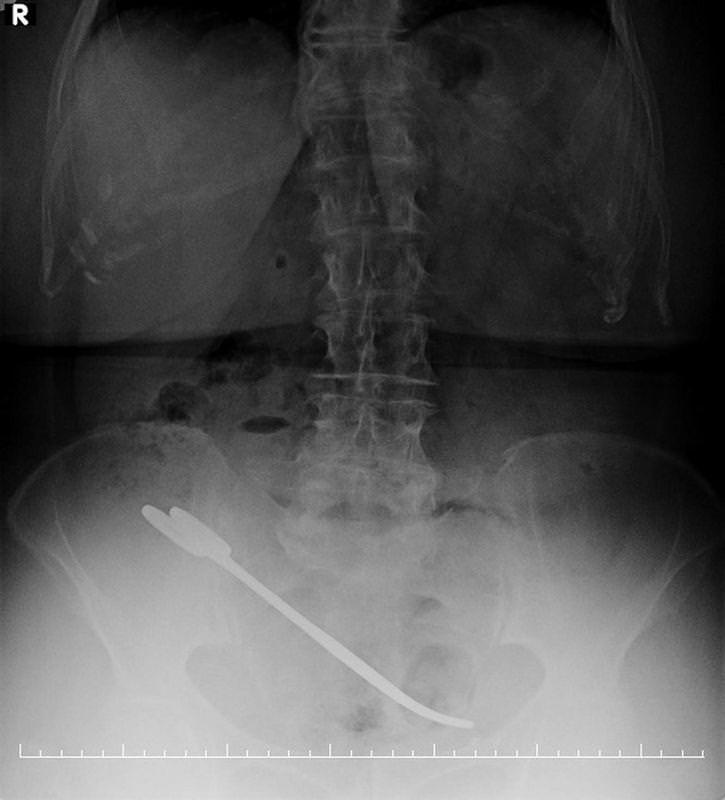

Özgül: “Röntgende “Sende makas var” dediler inanmadım korktum. Oğlum ne arıyor bende makas?” bu sorunun üstüne de aynı şekilde sende makas ver dediler.

67 yaşındaki Hanım Özgül 5 yıl önce rahim kanseri ameliyatı oldu. Kanserden kurtuldu ama artık yeni bir sağlık sorunu vardı. Özgül:”Her ay kontrole gittim. Kontrolde hiçbir şey çıkmadı. 6 senedir benim midem ağrıyor, karnım ağrıyor. Hiçbir şey yapamıyorum. ” Özgül, ameliyat sırasında karnında unutulan o makasla tam 5 yıl yaşadı. En sonunda şikayeti artınca başka hastaneye gitti. Röntgeni çeken görevli makası önce Özgül’ün cebinde zannetti.

Özgül:”Cebinde makas var, çıkart dediler yok oğlum dedim ben de makas yok dedim.” Makas cebinde değil içindeydi. Gerçek, röntgen ile anlaşıldı. Yaşlı kadın ameliyat olduğu hastanede yeniden ameliyat masasına yattı.